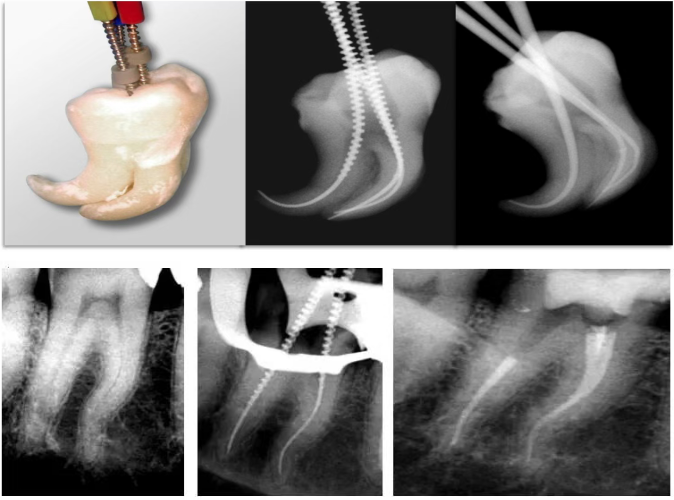

Gentlefile利用6500rpm高转速驱动,在离心力的作用下Gentlefile紧贴不规则根管壁进行预备清洁。

Gentlefile以6500高速旋转产生的离心力让锉体紧贴不规则管壁进行修形预备,达到3D清洁效果

而Gentlefile 超柔锉体利用离心力紧贴不规则的根管壁修形和清洁,同时利用Gentlefile高速旋转(6500 rpm)强力激活冲洗液进行清洁。

根据东京医科齿科大学的研究报告,相比于镍钛系统,GF系统锉体柔软、高转速、研磨式预备的特点有助于根管更好的清洁。用Gentlefile预备清洁效果更好,在根管中段的偏移更小。

Gentlefile柔韧度大,无需直线入路

Gentlefile可以45度角进入根管进行预备和清洁并且锉的柔韧度不受尺寸和锥度的影响